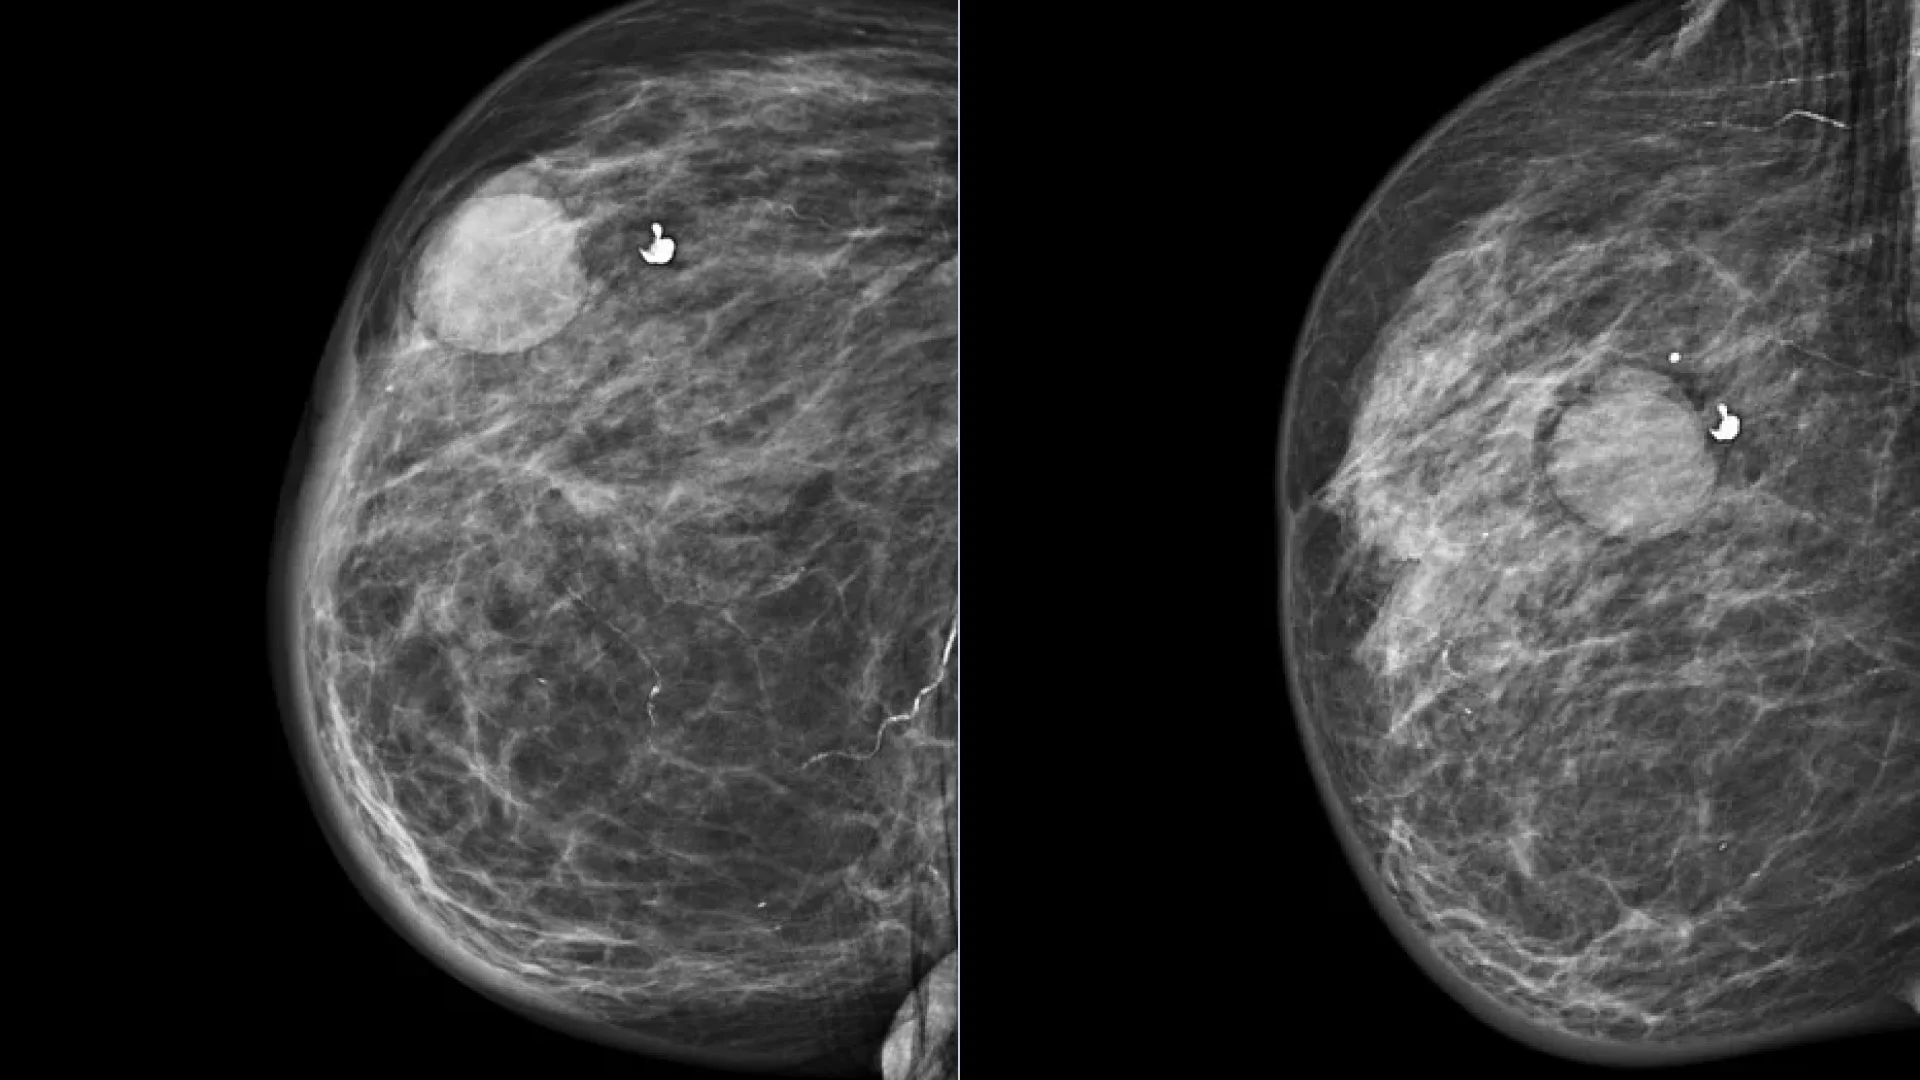

4. Mammography

Mammography is uninformative in the diagnosis of cystic breast masses. In the presence of complex and complicated breast cysts, according to ultrasound, mammography may be prescribed as a clarifying method for differential diagnosis with breast cancer.

Radiologically, large cysts are defined as round or oval masses of homogeneous structure with smooth, clear contours; small cysts are not radiologically defined. In patients of reproductive age, mammography is uninformative due to an evident glandular component in the structure of breast; therefore, this diagnostic method is more often used in postmenopausal patients.

Mammography of the right breast in two projections: a breast cyst

Mammography of the right breast in two projections: breast cyst. Author: Henry Knipe. Source: Radiopaedia. Simple Breast Cyst [12]